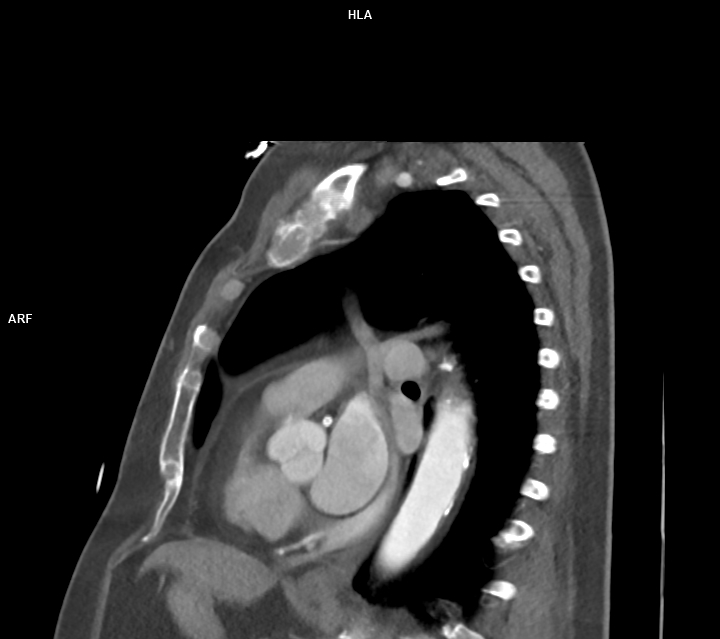

Figura 2: reconstrucție volumică din achiziție CT postcontrast

Discuţie caz nr 47: variantă anatomică de formare a sistemului venos cav inferior cu persistența de venă cavă superioară stângă – există varinate anatomice în care vena cavă superioară stânga este singurul element de drenaj al sângelui de la nivelul extremității cefalice și membrelor superioare. Este important de cunoscut la pacienții ce urmează proceduri interventionale / de cateterizare cardiacă sau la pacienții care au nevoie de cateter venos central.